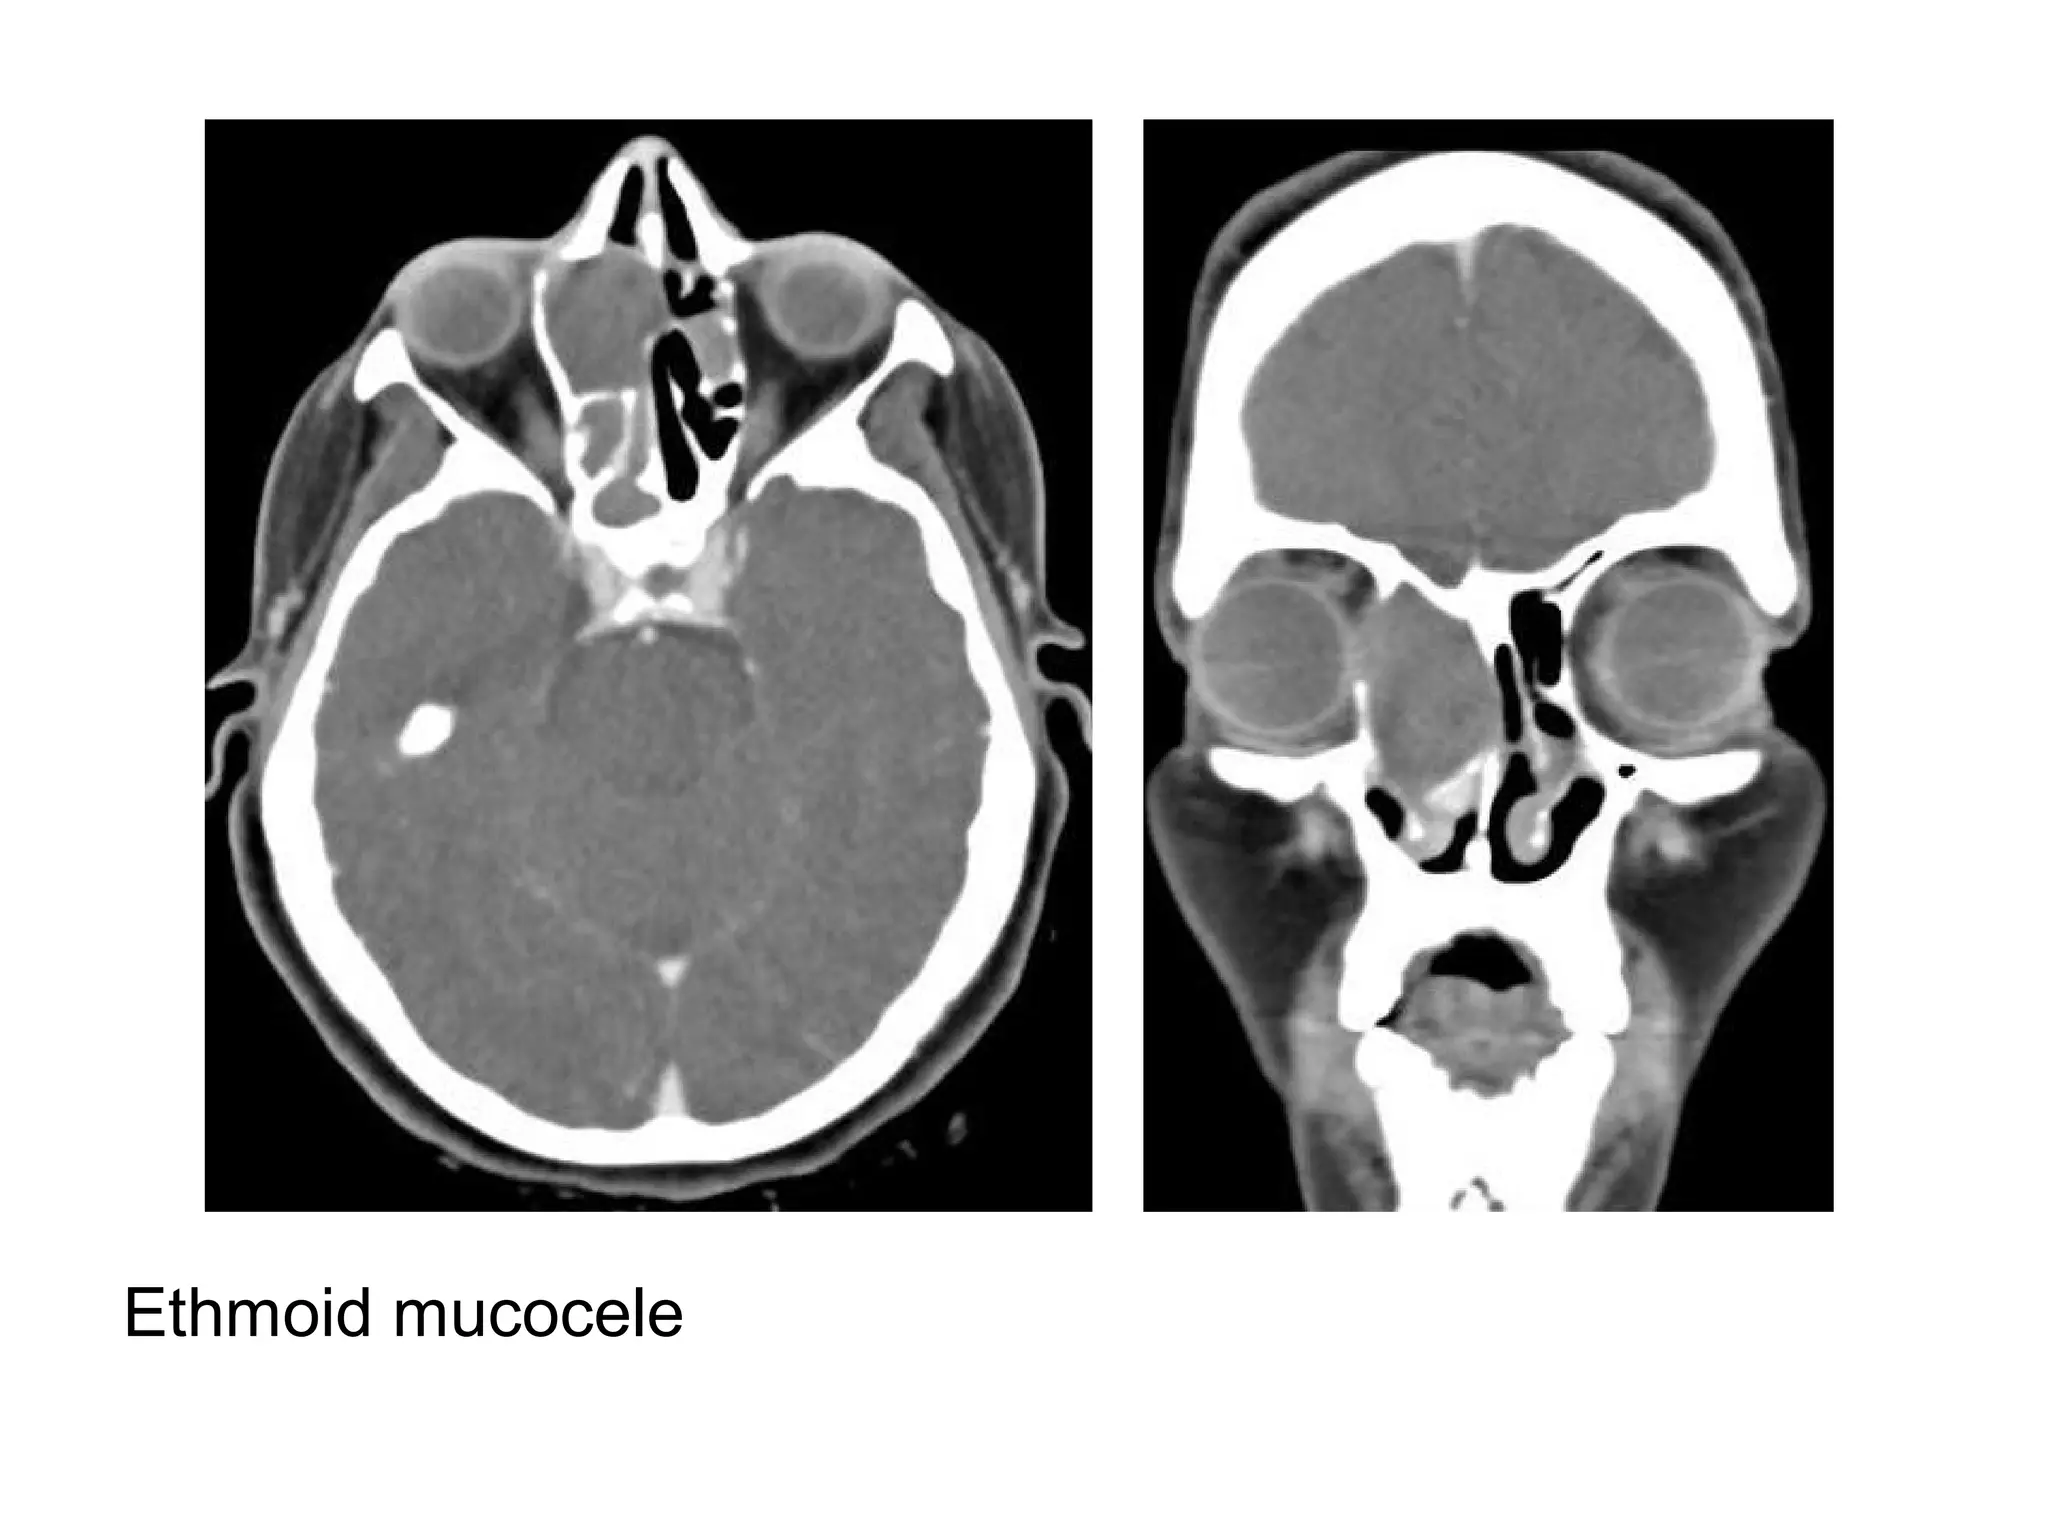

Ethmoid mucocele

Right ethmoid mucocele, coronal soft tissue (A) and axial bone

algorithm (B) CT images show a completely opacified, mucus-filled

and expanded right ethmoid sinus, focal dehiscence or erosion of

the right lamina papyracea (arrow, B) is seen